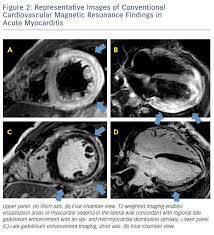

Kardio Mrt Myokarditis / Figure 8 From Cardiac Mri Of Acute Coronary Syndrome Semantic Scholar / Was heute alles möglich ist.